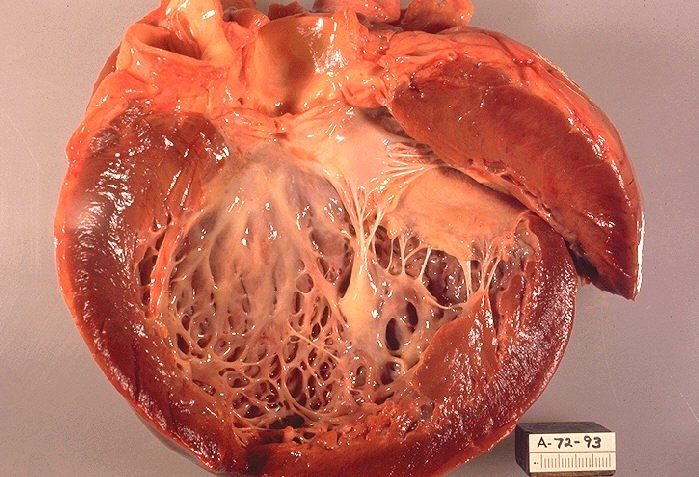

سه شکل شایع کاردیومیوپاتی٬ کاردیومیوپاتی گشادشده که شایعترین شکل کاردیومیوپاتی است، کاردیومیوپاتی هیپرتروفیک یا رشد دیواره و ضخیمشدن عضله قلب و نیز کاردیومیوپاتی محدودکننده (Restrictive) ( کاهش انعطافپذیری عضلات قلب) میباشد.

کاردیومیوپاتی گشادشده (DCM)